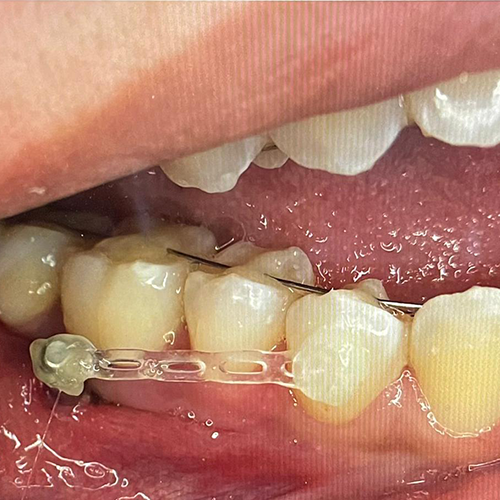

Comprueba en la práctica cómo el conocimiento se transforma en resultados reales a través de los casos de nuestros alumnos.

SALA DE PROCEDIMIENTOS

Siga clases prácticas y la evolución de casos clínicos reales directamente desde la clínica del Dr. Ary Nunes.